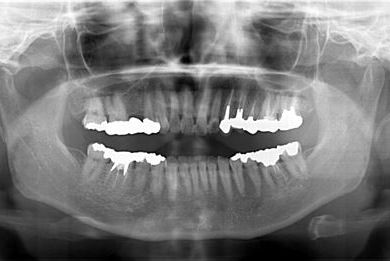

インプラントの症例写真 IMPLANT

骨再生インプラント治療

| 性別/年齢 | 女性 / 46歳 | ||||||||||||||||||||||||||||||||

| 主訴 | 歯ぐきがただれてる。歯が少しうずく。 | ||||||||||||||||||||||||||||||||

| 治療方針 | インプラント治療にて、機能的・審美的回復を行う。 | ||||||||||||||||||||||||||||||||

| 治療内容 | インプラント1本(GBR)、ハイブリッドセラミック1本 | ||||||||||||||||||||||||||||||||

| 総治療費 | 368,655円 | ||||||||||||||||||||||||||||||||

| 治療期間 | 7ヶ月 |